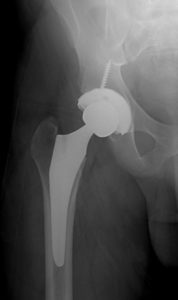

Hip replacement is a surgery whereby the ball and socket of the hip joint are replaced by artificial surfaces (commonly metal and plastic parts). The “ball” (femoral head) is removed and is replaced with an artificial ball that is connected to a stem that fits inside of the thigh bone (femur). A metal cup is placed into the socket and fit with a plastic liner that will articulate with the new artificial femoral head (figure 2).